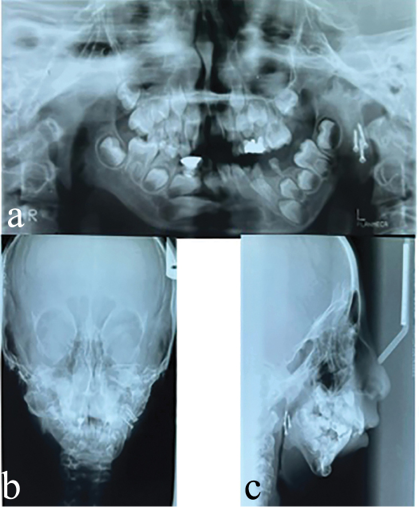

At age 7 (2008), condylectomy and costochondral graft surgery were performed. Almost 8 mm of the length of the right fifth rib, along with the attached cartilaginous part, was removed for grafting. Figure 1 shows the patient before the surgical procedure.

Figure 2 shows the panoramic, lateral, and PA cephalometric images after condylectomy and costochondral grafting.

Figure 1. The patient before surgery.

Figure 2. Panoramic, lateral, and PA cephalometric images after condylectomy and costochondral surgery.